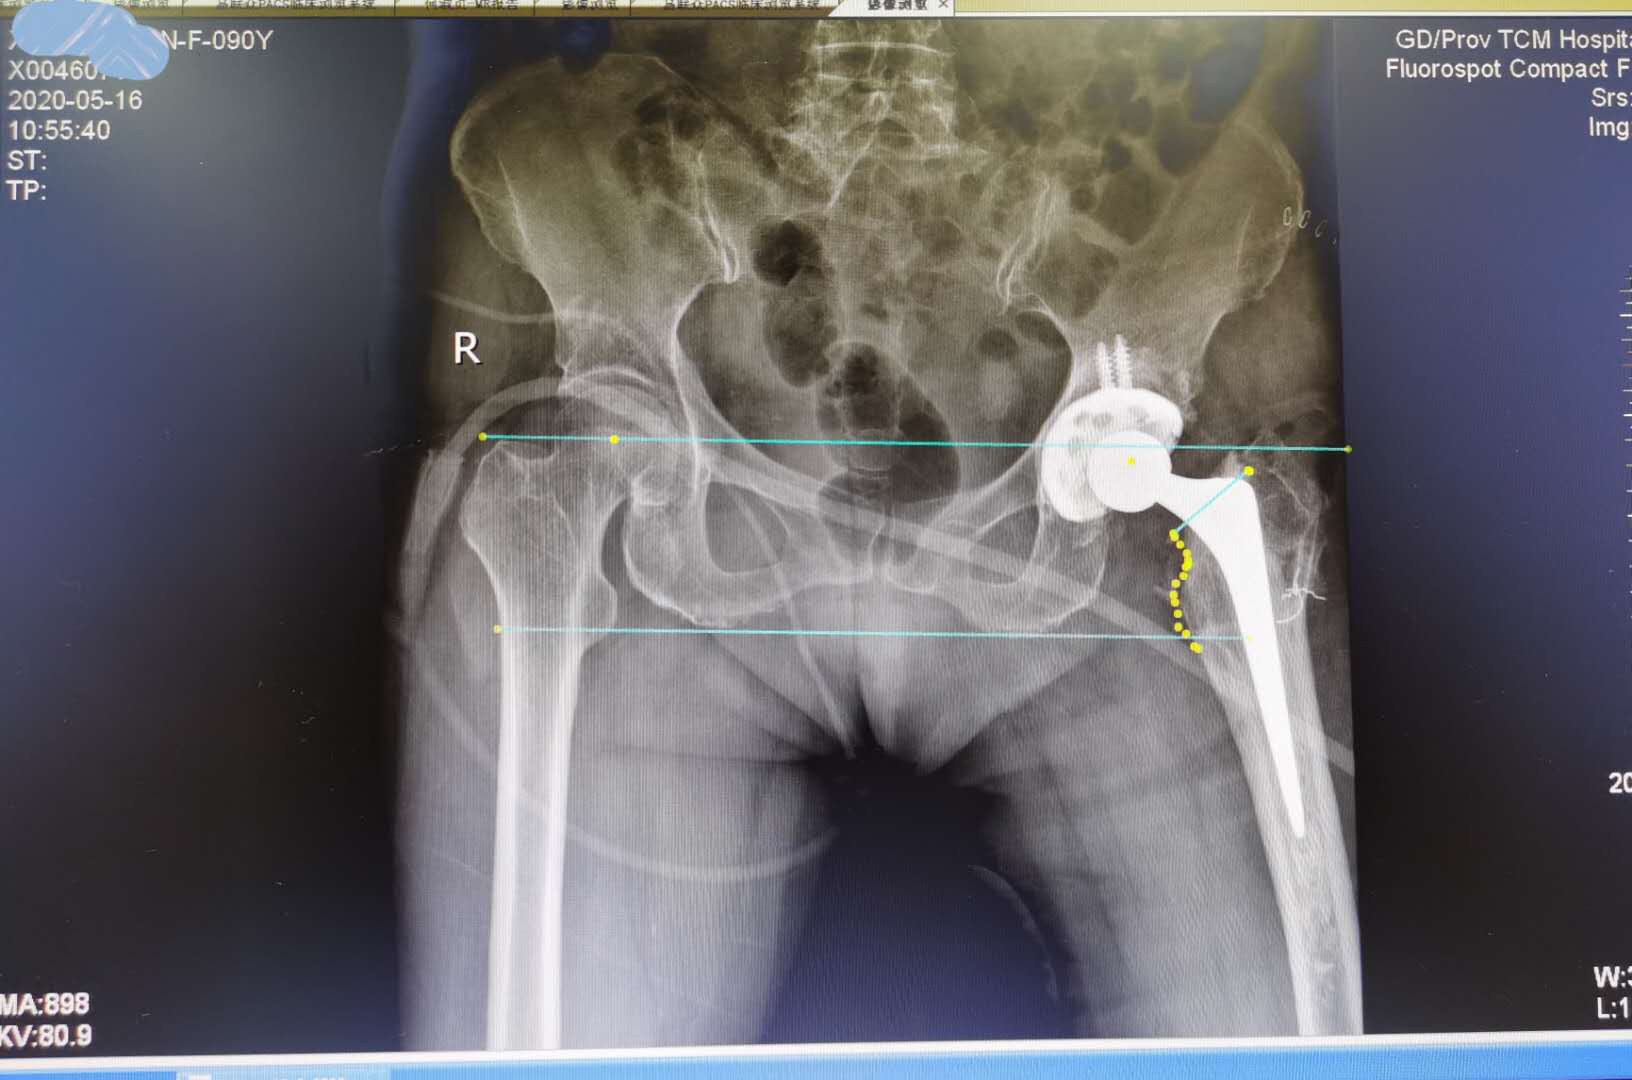

面对如此高龄的患者,手术不仅对患者来说是一种挑战,对医生来说也是一场严峻的考验,老人家的家属们纷纷请求行髋关节翻修。排除手术禁忌症后,5月15日在全麻下行左髋关节假体翻修术,术后恢复良好。

值得注意的是,术前评估很重要,病人即使90岁,但是此次左侧髋关节疼痛前,可以自己照顾自己。医师术前需要心肺功能评估,需要麻醉科等多学科配合,需要评估社会心理因素等做出超高龄关节置换翻修决定。... 围手术期安全很重要。#医联媒体超能团# #清风计划#